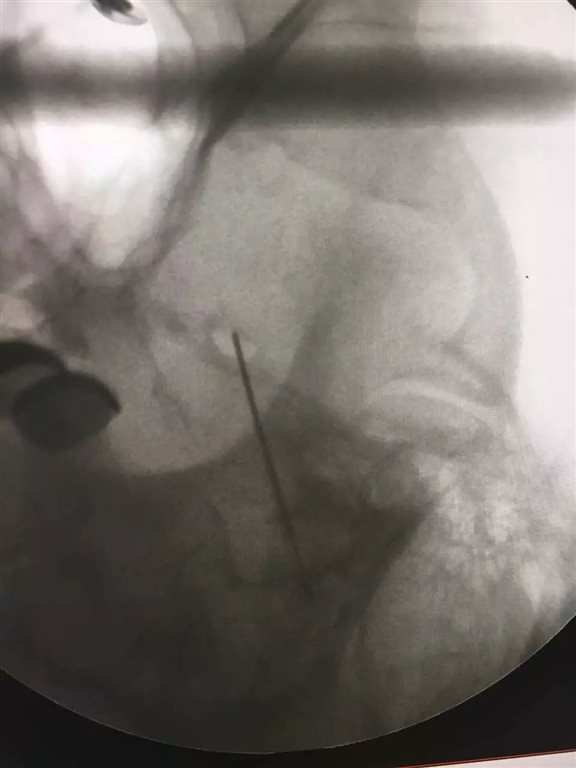

正位透视,看看侧位吧......

侧位透视,开始测试吧